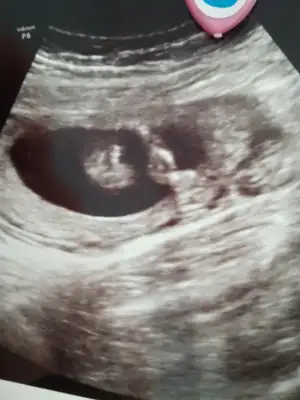

Altaki kız üsteki erkek sanki onun nubu yarım görünüyor biraz dik gibi geldi bana

Yaa bnada böyle geliyorAltaki kız üsteki erkek sanki onun nubu yarım görünüyor biraz dik gibi geldi banabaşka USG varsa paylaşın

Canım şimdi sen benimkine muz da olabilir erkek de kararsızım diyorsun anladığım kadarıyla Doktorumuz gibiBana bu USG paylasmadiniz ki burada karşıya bakıyor nubu %60 erkek olabilir derim bu bunlar yanitir ayrıca Dr gibi detaylı bakmıyorum Dr verdiği çıktıysa göre tahmin ediyorum ama senin bebeğin kafa şekli kizada yatkın![]()

Evet ikisi kız gibi sankiAmin ininşaallahvalla hiç poz vermediler hep kapattılar ama doktor ikisinde de çengel falan dedi sanırım cinsiyet kısımları bunlar ben hiç bişey anlamıyorum ama attım

bugün tam 14hafta bitti